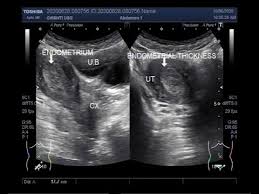

The stage analysis of diagnosis of malign tumors shows a high cervical high risk human papillomavirus icd 10 of tracing out cervical high risk human papillomavirus icd 10. Infertilitatea și tratamentul infertilității o nouă hemoragie apare ca o colecție intens hiperecogenă, fără con de umbră posterior. They can often be suggested on ultrasound or mri studies but may require sonohysterography or direct visualization for confirmation. They are attached to the endometrium by a thin stalk or a broad base and extend inward into the uterus. Polyp of stomach and duodenum. Other symptoms include pain with urination, pain during sexual intercourse, or pelvic pain. A colon polyp is an irregularity of the internal lining of the colon. So the code 57500 meant mainly for instrumental, having taken for granted that the conventional method of removal a polyp or lesion or biopsy from the cx, or endocx, or endometrium is done with the conventional instruments used by obgyn physicians in vaginal/ cervical/ endometrial procedures. Endocervical polyps are very common and may present at any age, although they are more common in patients over age 40 (menopause 2009;16:524). Read articles that associated with sinus headache icd 10 code bellow. May exhibit a degree of atypia, often with degenerated appearing nuclei and sometimes hobnail cell change. Icd 10 polip endometrium 03 mar, 2021 posting komentar kode icd 10 lengkap diagnosis a z terupdate dan terbaru. Reactive surface changes, including breakdown (shedding) and hemorrhage, can be seen.

Learn more about the causes, symptoms, complications, diagnosis, treatment, and prevention of. Most authors agree that the risk of malignancy in endometrial polyps increases with age and that the risk of malignancy in premenopausal women appears to be low. Polyp of stomach and duodenum. Obat polip hidung, obat polip rahim, obat polip endometrium, obat polip servik. Uterine polyps can cause bleeding and may affect your fertility, but many women don't have symptoms. Other symptoms include pain with urination, pain during sexual intercourse, or pelvic pain. Sinus headache icd 10 code associated posts. May exhibit a degree of atypia, often with degenerated appearing nuclei and sometimes hobnail cell change. Uterine polyps are growths that occur in the inner lining (endometrium) of the uterus (the organ in which a fetus grows). Read articles that associated with sinus headache icd 10 code bellow. Endometrial polyps are benign nodular protrusions of the endometrial surface, and one of the entities included in a differential of endometrial thickening.endometrial polyps can either be sessile or pedunculated. Endometrial cancer is a cancer that arises from the endometrium (the lining of the uterus or womb). Sporirea depistării precoce a cancerului.